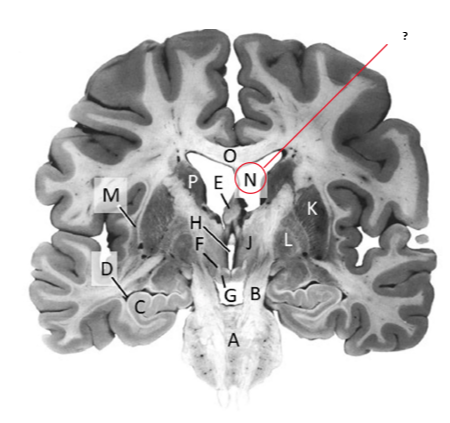

Name this and state its function.

Hippocampus.

Thalamus.

Third ventricle.

Caudate nucleus.

Name this and state its function. And what tract is involved?

Mamillary bodies.